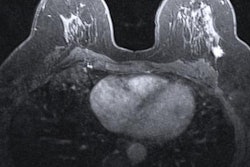

Although both MRI and ultrasound are capable of effectively imaging BI-RADS 3 lesions, each modality has respective differences in imaging features, which can be confusing for radiologists and clinicians to interpret. Arian and colleagues wanted to present MRI features of ultrasound-detected BIRADS-3 lesions and compare findings from both modalities among women with ultrasound-detected BIRADS-3 masses.

They looked at data from 123 ultrasound-detected BI-RADS 3 lesions in 67 patients with a median age of 38 years. The women who were focused on for the study included candidates of assisted reproductive therapy and patients with prior high-risk lesions.

The researchers found that MRI agreed with ultrasound on 87% (n = 107) of cases. MRI downgraded another 12 cases (9.8%) to BI-RADS 2 and upgraded four cases (3.3%) to BI-RADS 4.

Additionally, the median size of the lesions was 9 mm in MRI and 9 mm in ultrasound, which the team wrote was "highly" correlated, yielding a Spearman correlation coefficient of 0.889 (p < 0.001).

The group also found that MRI evaluation revealed two cases of deep lesions that were missed in ultrasound imaging.